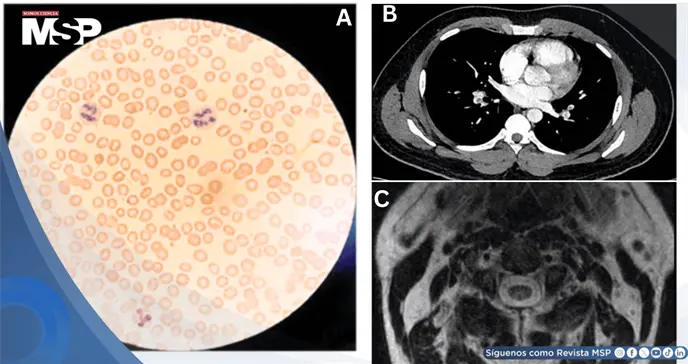

Los estudios de laboratorio evidenciaron anemia megaloblástica con hemoglobina de 10.6 g/dL y volumen corpuscular medio elevado de 100 fL. El frotis periférico demostró neutrófilos hipersegmentados, hallazgo característico de la deficiencia de vitamina B12.

Los estudios de laboratorio revelaron anemia megaloblástica con hemoglobina de 10.2 g/dL y volumen corpuscular medio elevado de 105.8 fL. Los marcadores bioquímicos demostraron deficiencia severa de vitamina B12 con nivel menor a 146 pg/mL, ácido metilmalónico marcadamente elevado en 8.92 µmol/L y homocisteína en 127 µmol/L, aproximadamente ocho veces por encima del límite superior normal. La prueba PCR para COVID-19 resultó negativa.